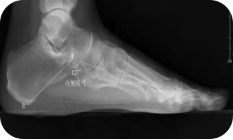

X线测量法:第一跖骨距骨角、距舟覆盖角及跟骨倾斜角等参数的测量,对足进行影像学评估

足负重前后位、足负重侧位(足内弓角测量、外弓角测量、跟骨倾斜角)